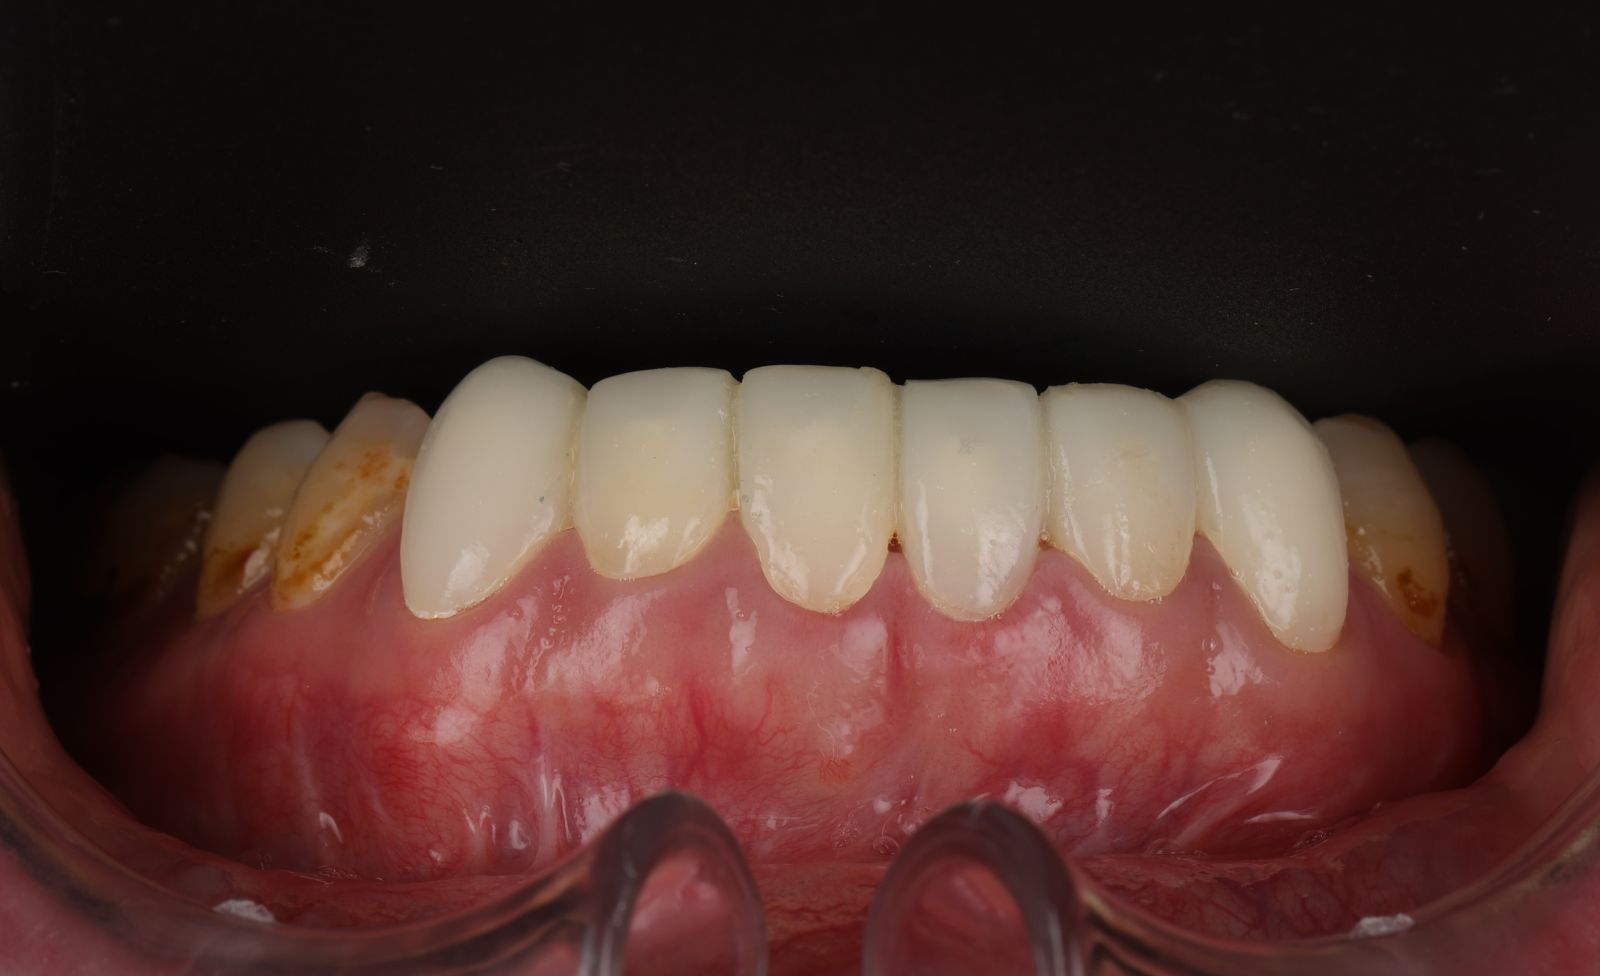

- 先把舊的假牙拆除後換成臨時假牙,期間先做冷光美白讓牙齒的基礎顏色變白,用保養型冷光美白,讓其他自然牙的部分可以白2~3個色階。一段時間讓顏色穩定後就可以當作正式全瓷冠的顏色參考。

經過數位微笑曲線設計,選擇自己喜歡的色階後就可以製作適合自己的美學全瓷牙囉!全瓷冠經過特殊處理呈現的通透感,讓牙齒白而自然透亮。